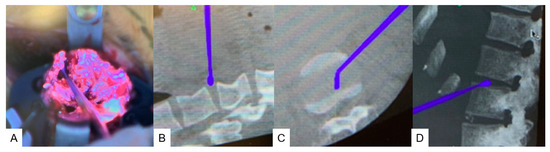

2.4. Surgery

2.4.1. Anterior Discectomy

2.4.2. Posterior Osteotomy